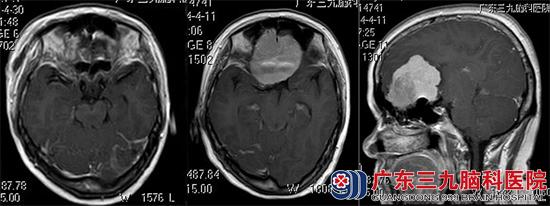

一月前开始出现间断性头痛,伴有嗅觉减退,当地医院头颅CT检查结果:双侧额部巨大占位性病变。入住广东三九脑科医院,进一步头颅MR检查提示:双侧额底部示一团块状占位性病变,范围约5.87cm×5.20cm×5.24cm,考虑脑膜瘤可能性大。

▲手术前